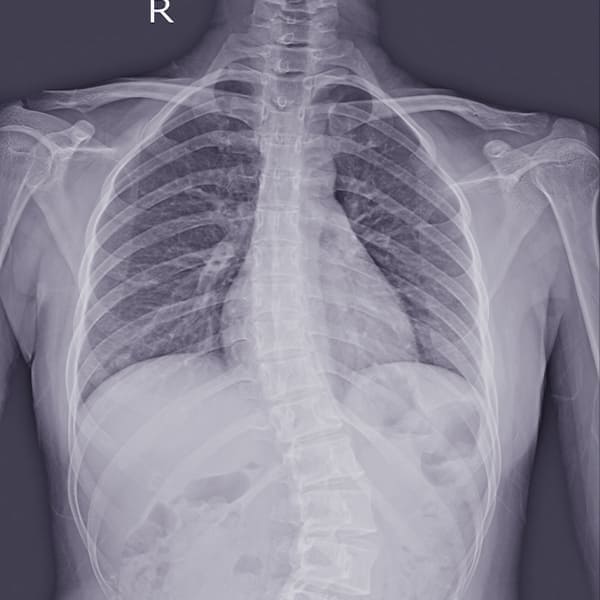

Resección de Tumores de Columna Vertebral

Eliminación de tumores para mejorar la función neurológica y reducir el dolor.